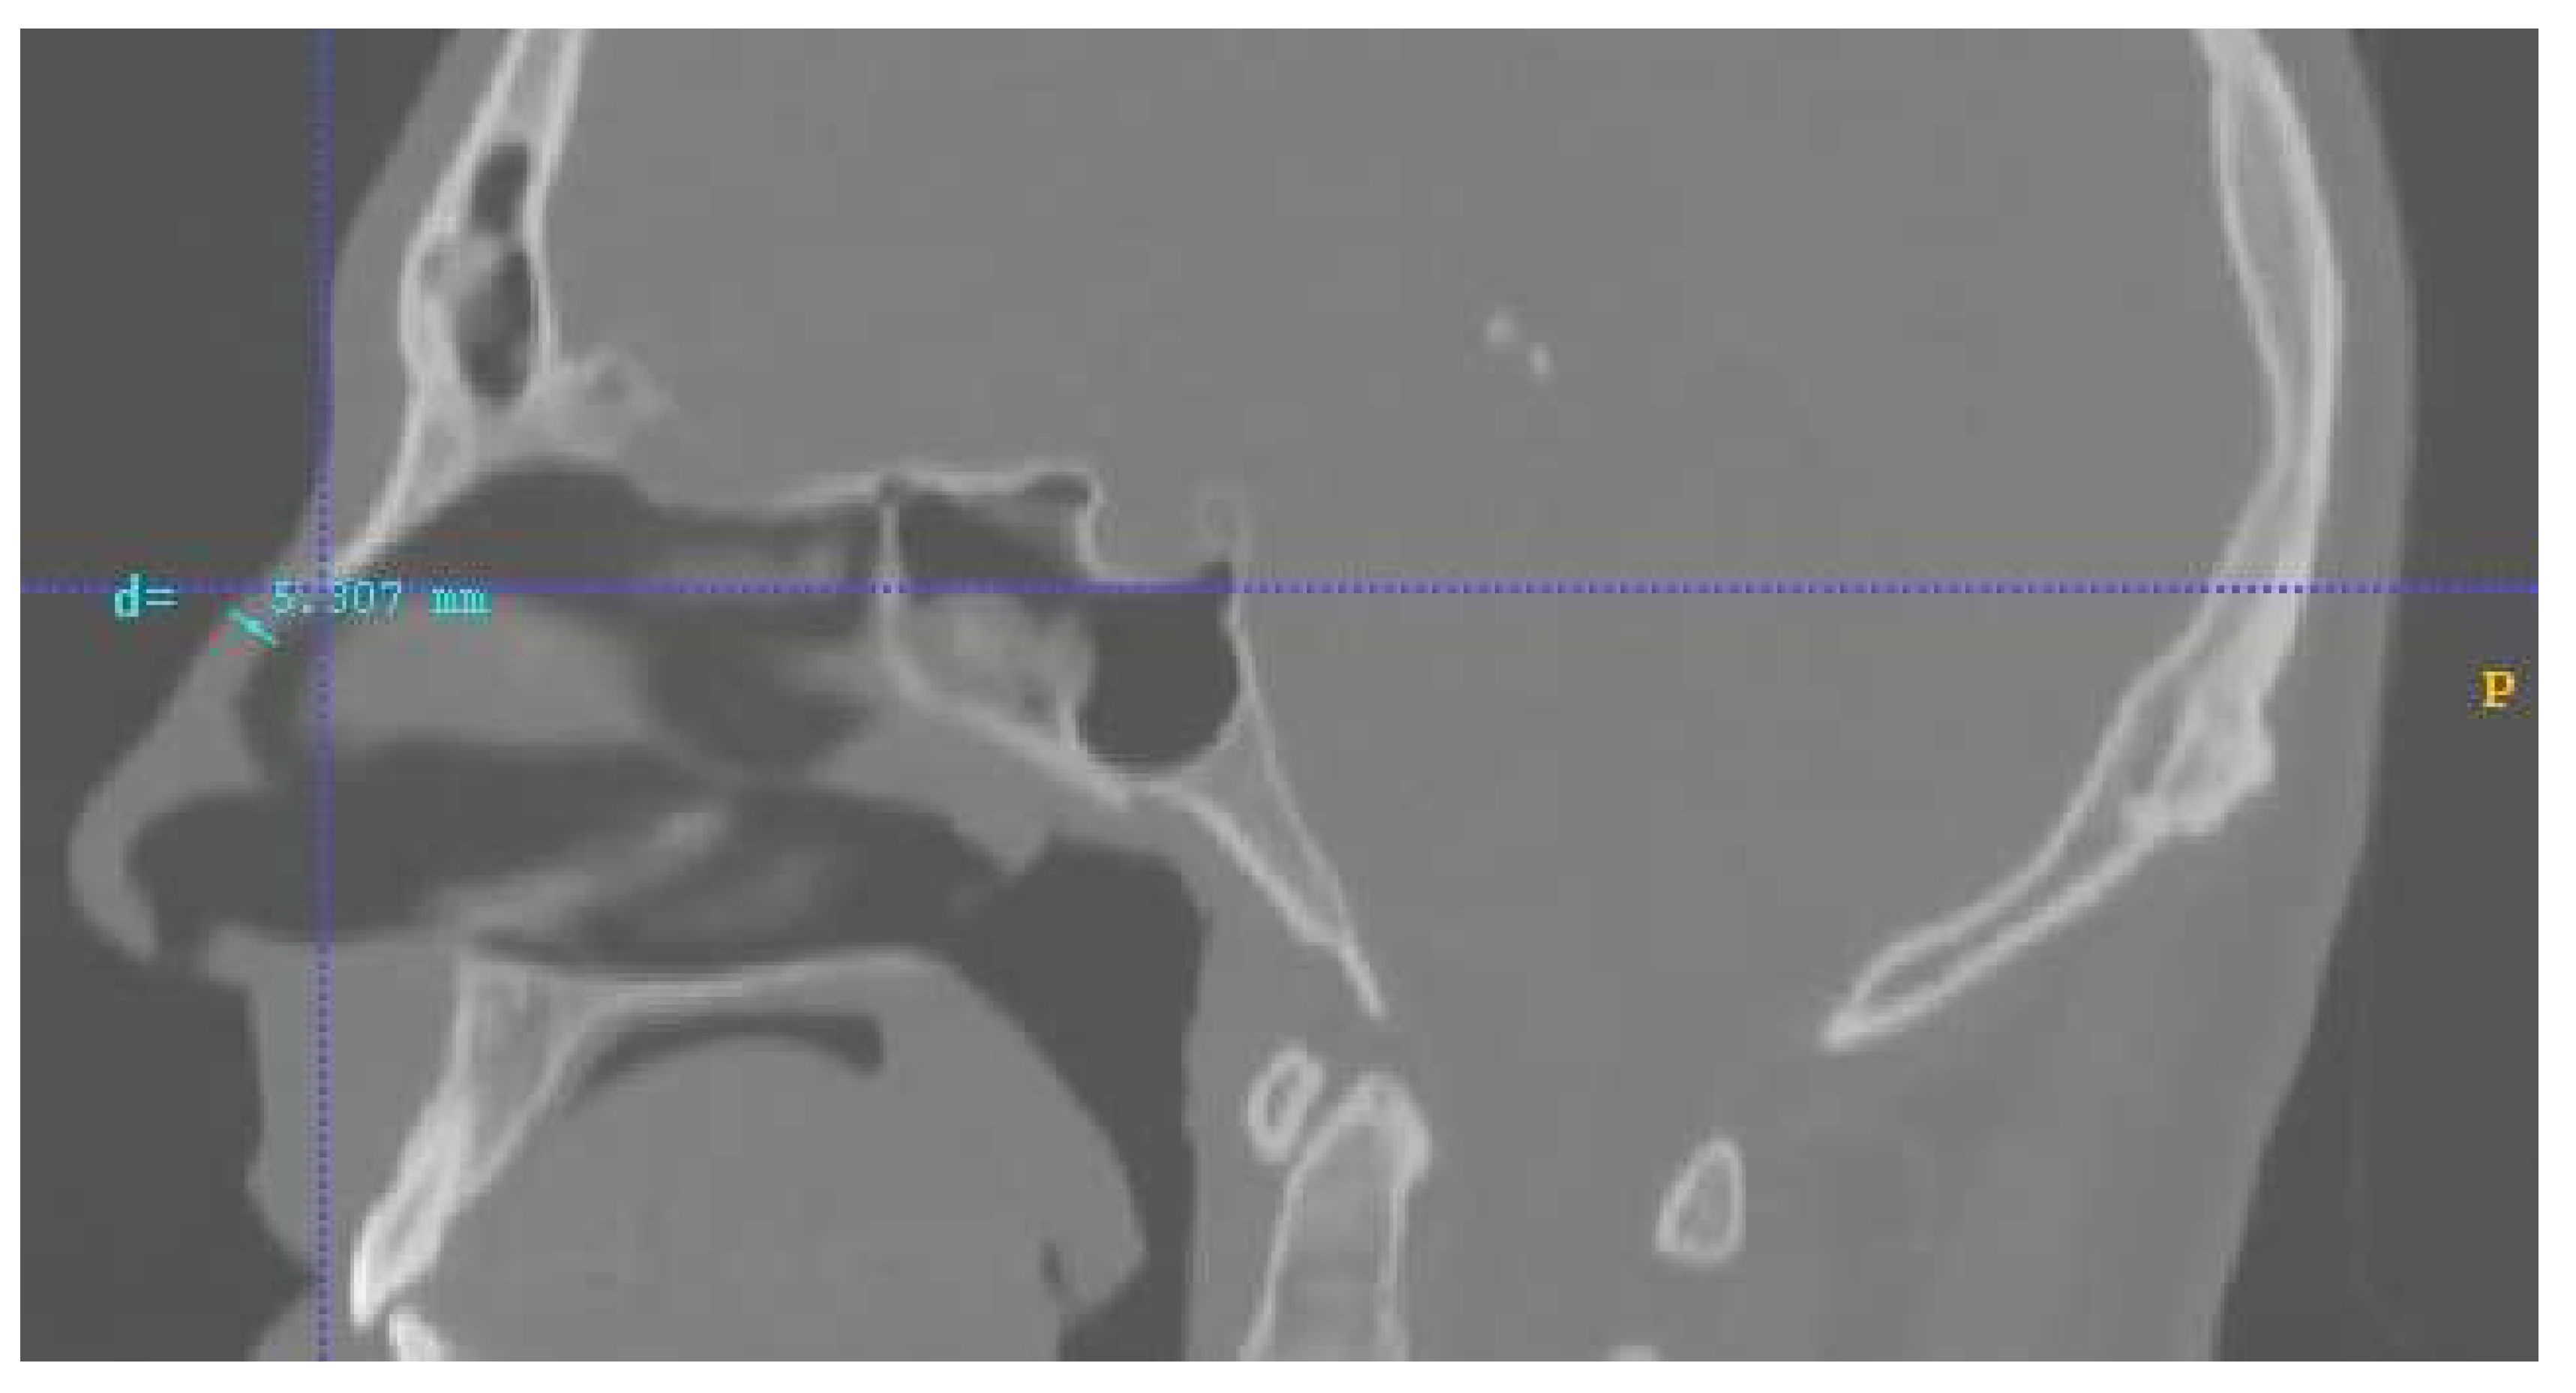

This section offers a detailed presentation of the materials and the methods implemented in the analysis. More specifically, the nose model construction, as well as the protocols of this study are described, along with the software and numerical details of the analysis. Lastly, the parametrized analysis is outlined, including the fluid dynamics, the magnetostatic and the particle tracing approaches. In this study, three different delivery approaches were analyzed based on a layout of two permanent neodymium-iron-boron (NdFeB) magnets (with a remanence of 1.2 T) placed on the nasal septum (Figure 1). The geometry was reconstructed from a real CT head image. For all protocols, the delivery efficiency was calculated on the olfactory region as the percentage of particles reaching the olfactory region of the total number of particles released in the nose.

Lastly, another important factor that should be discussed and clarified is the distance of the magnets. In this research, the approximated distance of the magnets’ center of mass from the nasal septum was set at d = 5 mm. This value is the distance between the inner surface of the nasal septum and the outside part of the human nose septum, according to the given human geometry, on which the magnets were placed. In Figure 6, this distance is illustrated with a blue line. That is why the distance value was set at approximately equal to 5 mm. The anatomic geometry of the nose as well as the individual inter-facial differences change this distance slightly from patient to patient. Hence, taking into consideration the fact that the magnetic field is proportional to 1/d2 and that the magnetic force is analogous to the magnetic field, we concluded that increasing or decreasing this distance it would strongly affect the results. Specifically, setting the magnetic layouts within the scope of a realistic distance factor d can exclude overestimated or underestimated values of delivery efficiency. (This could also be a possible contribution to the low efficiency achieved by the investigated protocols in comparison with similar work for similar magnetic field and particle size values [11,12]). Additionally, the maximum distance from the upper part of septum-radix to the anterior edge of the pronasale in this model was approximately 5 mm. That is the reason why the investigated magnetic layouts consisted only of one magnet and had a maximum length of 5 mm. Moreover, in our lab we possess the permanent magnets involved in the analysis, and this was an additional reason for selecting the forementioned magnets’ characteristics; that is, in order to support a possible future experimental analysis for result verification. The following table summarizes a comparison of the main contributions of our work with those reported in the literature regarding the state of the art (Table 3).

Figure 1. The general layout of the protocols analyzed. A permanent magnet is placed on the nasal septum (orange). The red circle indicates the olfactory region which occupies about 8% of the total nasal passage surface.

Figure 6. Distance from the outside nose septum to the nasal septum in human geometry. This distance of approximately 5 mm (blue line) was used as the distance of the magnets from the nasal geometric volume for the numerical analysis.